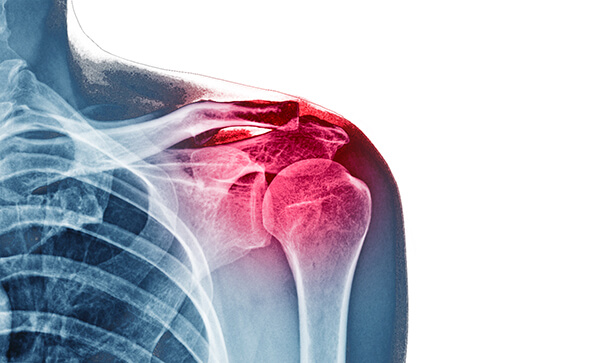

1. Pathologies of the Shoulder Joint – Part 4 By Dr. Gursimran Singh Anand

Shoulder pain is common, but interpretation must be precise. This session focuses on imaging-based diagnosis with exam relevance.

Key takeaways:

• Systematic radiological evaluation of shoulder disorders

• Role of X-ray, MRI & Ultrasound

• Key imaging signs of common shoulder pathologies

• Differentiating rotator cuff, labral & joint disorders

• High-yield points for Radiology, Orthopedics & Sports Medicine exams

Ideal for radiology residents and exam aspirants.